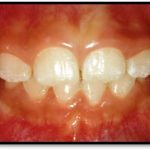

Treatment and Services